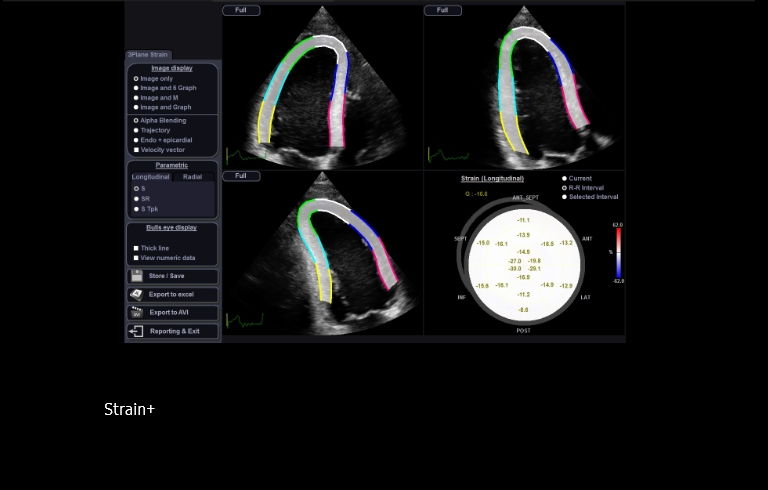

Strain+ ¹

Quantify wall motion of the left ventricle

Strain+ ¹ is a quantitative tool for measuring global and segmental wall motion of the left ventricle (LV). In Strain+ ¹, three standard LV views and a Bull's Eye are displayed in a quad screen for easy and quick assessment of the LV function.